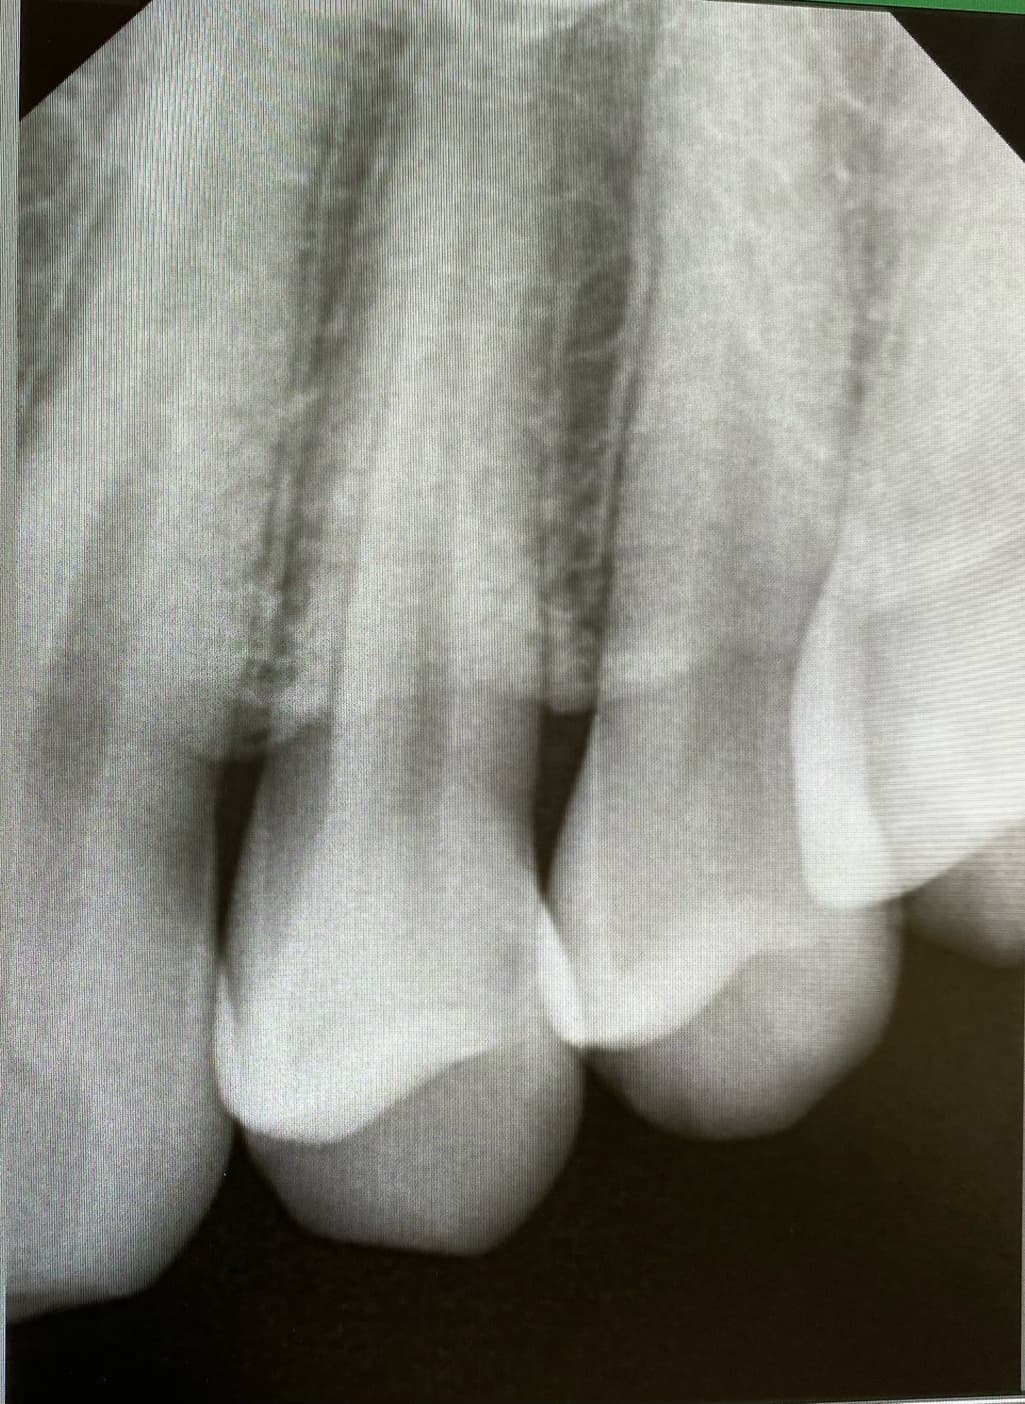

1번 치과는 왼쪽 위 4번째 안쪽면에 인접면 충치

육안상으로보면 치아 사이에 충치가 잇는거 같습니다. 관리를 잘하시면 진행이 안되겟지만 관리가 안되면 충치 진행이 빨라져서 신경치료를 해야될수도 잇으니 저라면 미리 치료를 하라고 권유할것같습니다 .

육안으로 봤을 경우에는 인접면에 충치가 있는 것으로 보이긴 합니다. 하지만 엑스레이 사진상으로 크게 보이지 않기 때문에 관리를 해서 사용할 수 있는 경우도 있습니다. 충치가 더 커지는 것을 방지하기 위해 예방적으로 치료를 하고자 한다면 치료가 필요할 수 있으며 그렇지 않다면 관리를 하면서 상태를 지켜볼 수 있습니다.